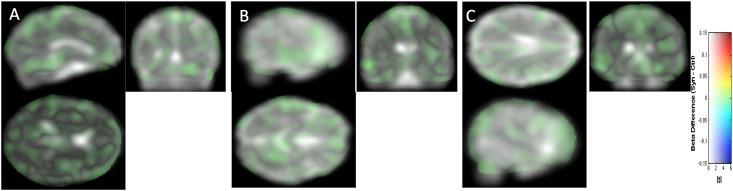

Several publications have reported structural changes in the brain of synesthetes compared to controls, either local differences or differences in connectivity. In the present study, we pursued this quest for structural brain differences that might support the subjective experience of synesthesia. In particular, for the first time in this field, we investigated brain folding in comparing 45 sulcal shapes in each hemisphere of control and grapheme-color synesthete populations. To overcome flaws relative to data interpretation based only on p-values, common in the synesthesia literature, we report confidence intervals of effect sizes. Moreover, our statistical maps are displayed without introducing the classical, but misleading, p-value level threshold. We adopt such a methodological procedure to facilitate appropriate data interpretation and promote the "New Statistics" approach. Based on structural or diffusion magnetic resonance imaging data, we did not find any strong cerebral anomaly, in sulci, tissue volume, tissue density or fiber organization that could support synesthetic color experience. Finally, by sharing our complete datasets, we strongly support the multi-center construction of a sufficient large dataset repository for detecting, if any, subtle brain differences that may help understanding how a subjective experience, such as synesthesia, is mentally constructed.

一些出版物报道了与对照组相比,联觉者大脑的结构变化,无论是局部差异还是连接差异。在本研究中,我们追寻这些可能支持联觉主观体验的结构脑差异。特别是,我们首次在这个领域比较了对照组和字母-颜色联觉者群体的每侧半球的 45 个脑沟形状,以研究脑折叠。为了克服仅基于 p 值的数据分析中存在的缺陷,这种方法在联觉文献中很常见,我们报告了效应大小的置信区间。此外,我们的统计映射是在不引入经典但具有误导性的 p 值水平阈值的情况下显示的。我们采用这种方法来促进适当的数据解释并推广“新统计学”方法。基于结构或扩散磁共振成像数据,我们没有发现任何强烈的大脑异常,无论是在脑沟、组织体积、组织密度还是纤维组织方面,这些都可以支持联觉颜色体验。最后,通过共享我们的完整数据集,我们强烈支持建立一个足够大的多中心数据集存储库,以检测任何可能有助于理解像联觉这样的主观体验是如何在心理上构建的细微大脑差异。